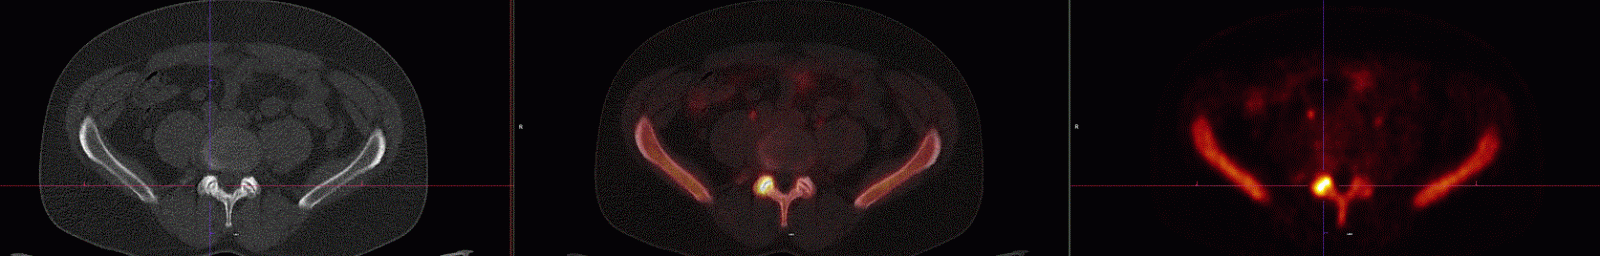

Vyšetření bylo indikováno k lokalizaci příčiny bolestí bederní páteře před případnou neurochirurgickou intervencí. Na dříve provedené MR odhalena degenerativní diskopatie L5/S1 se změnami Modic I.

Vlevo CT složka, vpravo PET složka a uprostřed fúze hybridního PET/CT vyšetření. V horní řadě je transverzální řez (pohled odspodu) vedený intervertebrálním skloubením L4/5, kde je vpravo patrna intenzivní akumulace radiofarmaka. Ve spodní řadě je koronární řez (pohled zepředu), kde je vlevo při intervertebrálních plochách obratlů L5 a S1 rovněž patrna intenzivní akumulace radiofarmaka. Obě ložiska představují vysokou osteoblastickou aktivitu při aktivních degenerativních změnách.